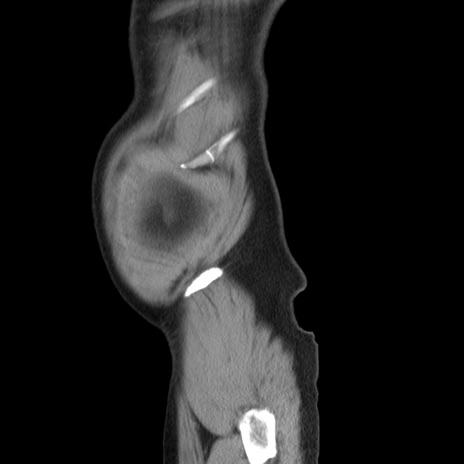

症例20(矢状断像)

【症例】 60歳代男性

【主訴】 腹部膨満、嘔吐

【現病歴】5日前頃より倦怠感を認め食事量減少し4日前の朝嘔吐、食事摂取困難となった。 3日前近医受診し点滴施行され整腸剤などを処方された。 当日他院を受診し、腹部膨満著明、炎症反応の上昇(CRP10.8、WBC11200)あり、紹介受診となる。

【身体所見】 意識JCS1 受け答えがはっきりしないBP 111/57mHg、 P 67bpm、、BT35.2°C、SpO2 97%(RA)、 腹部:膨隆、打診で鼓音あり、全体的に圧痛有り、腸蠕動音(-)、反跳痛ははっきりせず。

【データ】WBC 11400、CRP 14.20